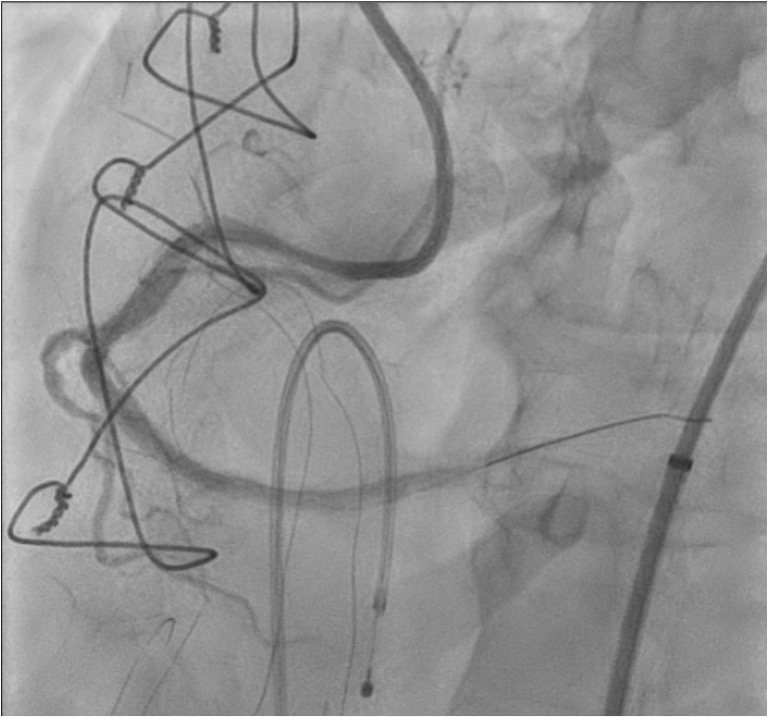

Right femoral arterial access was taken with 7F long sheath (45cm) and RCA was engaged with 7F AL 3.5 catheter. We failed to cross proximal lesion with Rinato wire (Asahi Intecc, Japan) but crossed with Fielder XT-R (Asahi Intecc, Japan). We had difficulty in crossing the distal lesion due to inadequate guide support and inability to deliver microcatheter beyond proximal calcific lesion. Proximal lesion was predilated with 2.5 mm NC balloon but the balloon got ruptured. Fielder XTR wire was exchanged with Rota floppy wire (Boston scientific, Japan) with corsair microcatheter (Asahi Intecc, Japan) delivered just beyond proximal lesion. Temporary pacemaker inserted and Rotablation of the proximal RCA lesion was done with 1.5 mm Rota burr. Post proximal lesion modification corsair could be delivered to Distal lesion, and lesion crossed with Ultimate Bros 3 (Asahi Intecc, Japan) followed by de-escalation to Fielder XT-R wire. The proximal lesion was then dilated with 3.5x10mm Wolverine Cutting balloon (Boston Scientific, Ireland) to deliver a 7F Guideliner beyond the proximal lesion for better support to further gear advancement. As 1mm balloon stuck within the distal lesion, grenadoplasty was performed followed by an exchange to rota wire with corsair. Rotablation of distal RCA lesion was done with 1.5 mm burr through guide extension. Further dilatation of distal lesion was done with 3mm IVL balloon followed by stenting with 3.25 x 28 mm drug-eluting stent with good TIMI 111 flow.

Sequential rotablation can be used in tandem calcified lesions when proximal lesion is obstructing gear delivery beyond. Guide extension facilitates burr delivery to the region of interest and avoids unintentional ablation of vulnerable zones in proximal vessel. Operator must be aware of burr compatibility information and preferred method of burr delivery.